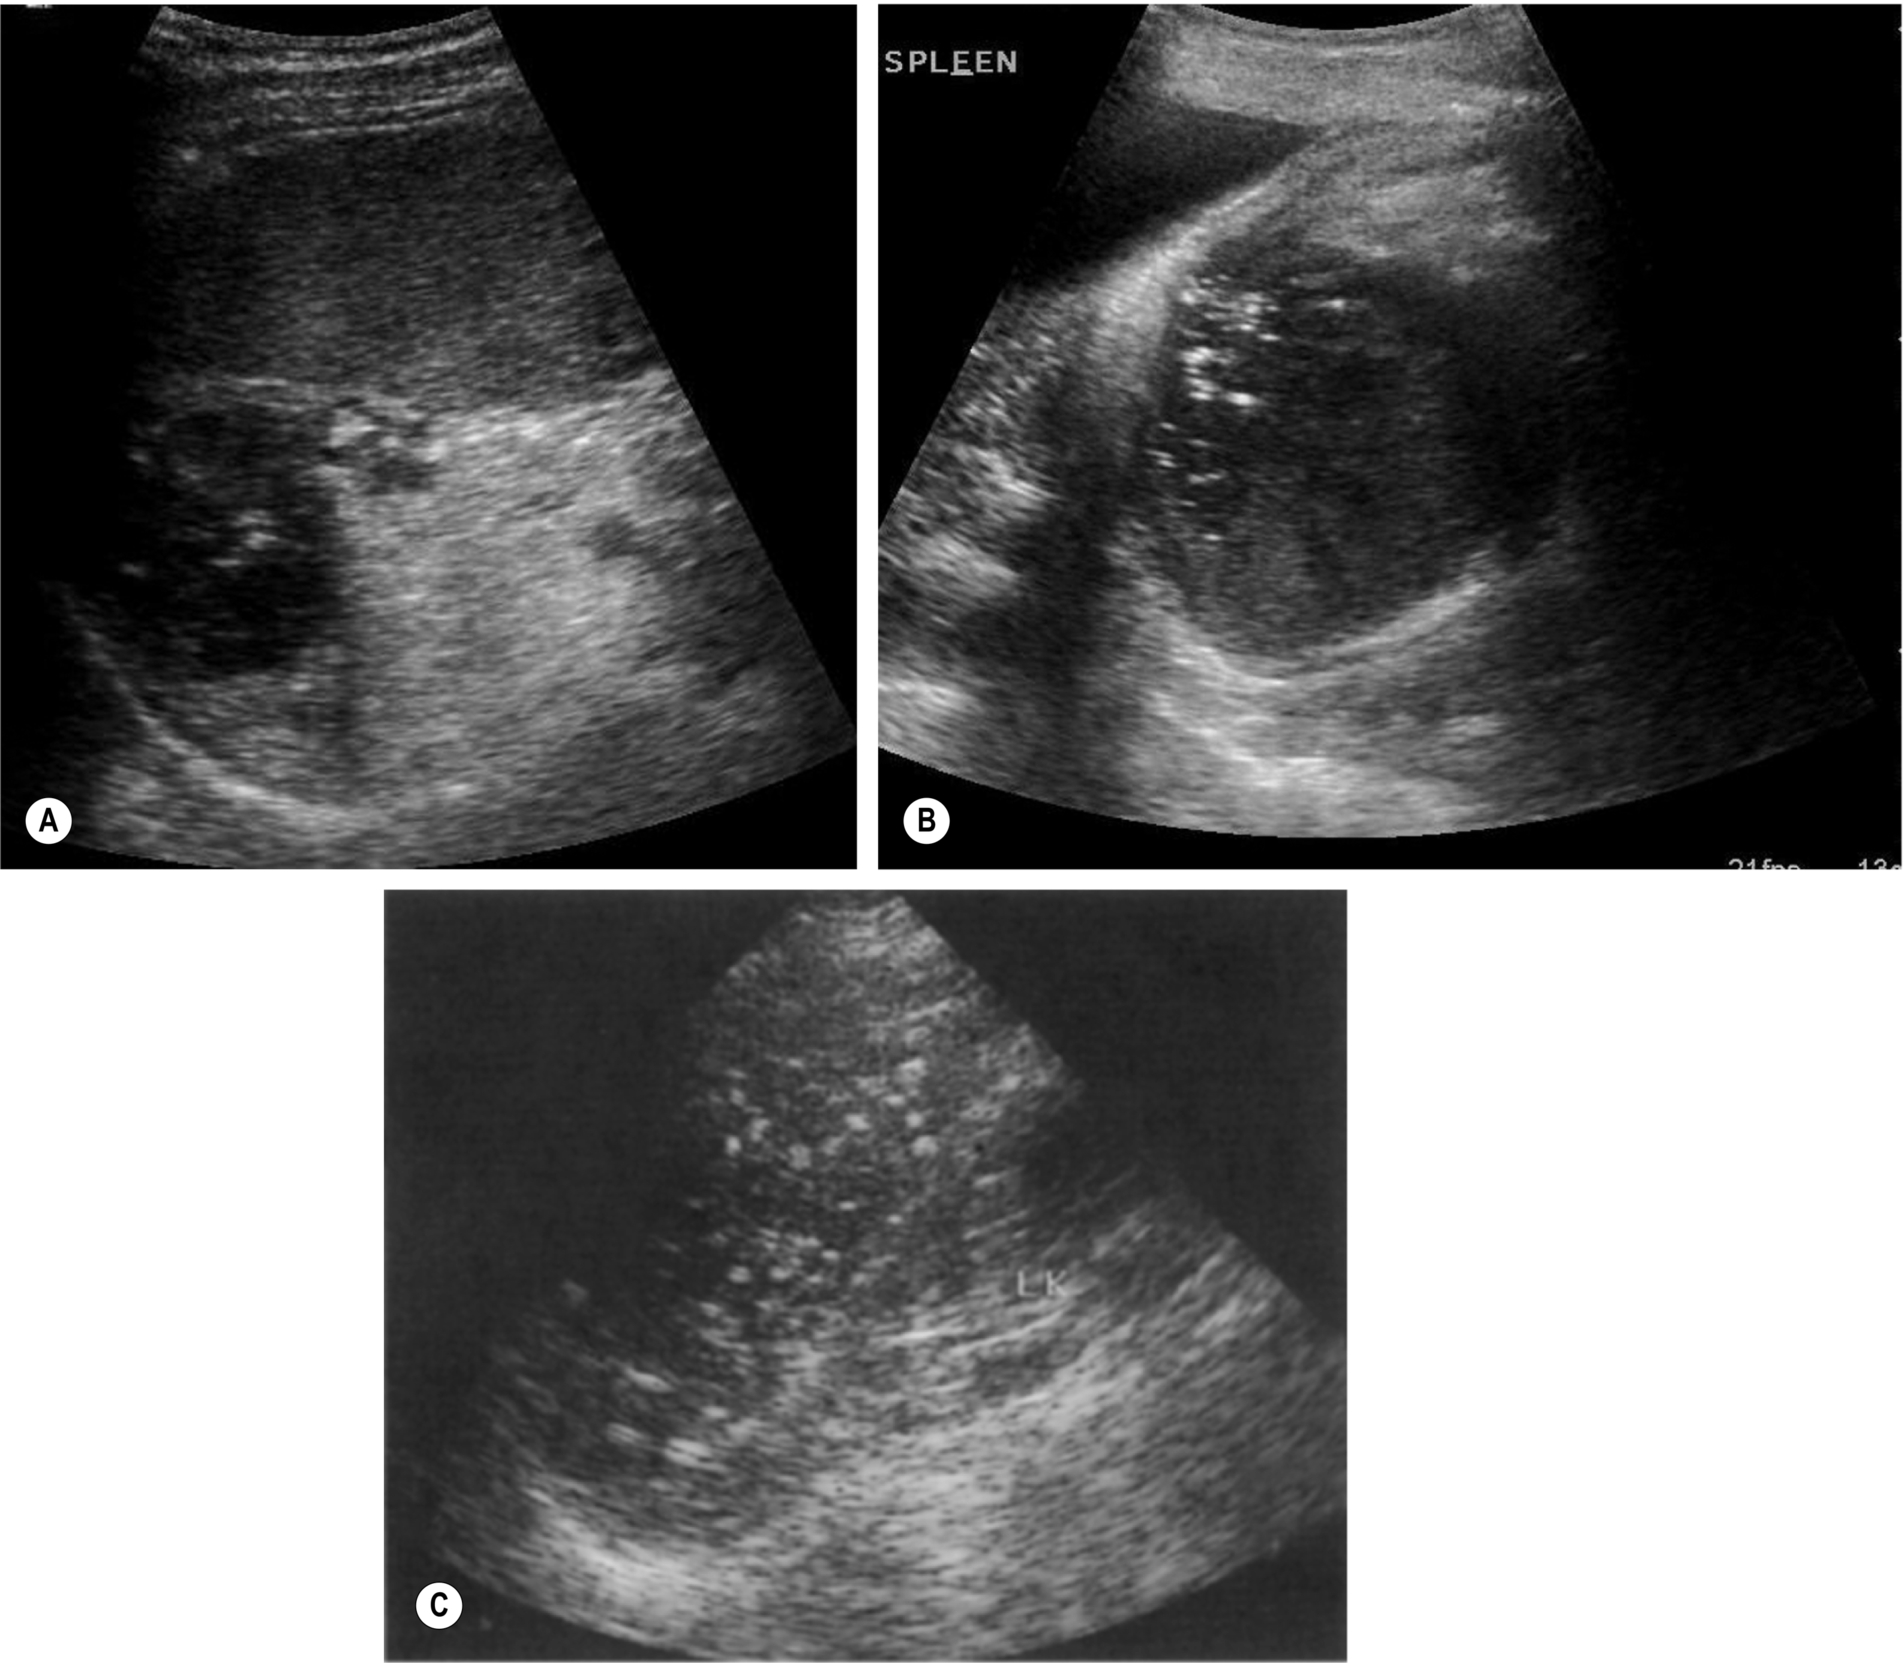

The main splenic artery and vein and their branches may be demonstrated at the splenic hilum (Fig. 5.1A–C). The spleen provides an excellent acoustic window to the upper pole of the left kidney, the left adrenal gland, and the tail of the pancreas.

Lymphoma is the most common malignant disease affecting the spleen (Fig. 5.3). Malignant cells can infiltrate the spleen, lymph nodes, bone marrow, and thymus and can also involve the liver, gastrointestinal tract, kidney, and other organs. Approximately 3% of malignant diseases are lymphomas. However, a primary splenic lymphoma is rare, constituting 2% of all lymphomas and 1% of all non-Hodgkin’s lymphomas.6 A primary splenic lymphoma diagnosis is made when the lymphoma is contained within the spleen with no distant spread or only spread to the lymph nodes within the hilar region. Biopsy under ultrasound guidance can be performed and is considered a relatively safe procedure.

Patients may present with a varied and broad spectrum of appearances in lymphoma (Fig. 5.3). In many cases, the spleen is not enlarged and shows no acoustic abnormality.11 Lymphoma may produce a diffuse splenic enlargement with normal, hypo-, or hyperechogenicity. In patients with hematological conditions, it is important to consider splenic volume as a way to show the progression of disease.

Although lymphoma usually has a diffuse effect on the spleen, focal lesions may also be present. They tend to be hypoechoic and hypovascular and may be single or multiple. In larger lesions, the margins may be ill-defined, and the echo contents vary from almost anechoic to heterogeneous, often with increased through transmission. In such cases, they may be similar in appearance to cysts. However, the well defined capsule is absent in lymphoma, which has a more indistinct margin.12 Smaller lesions may be hyperechoic or mixed. Tiny lymphomatous foci may affect the entire spleen, making it appear coarse in texture.